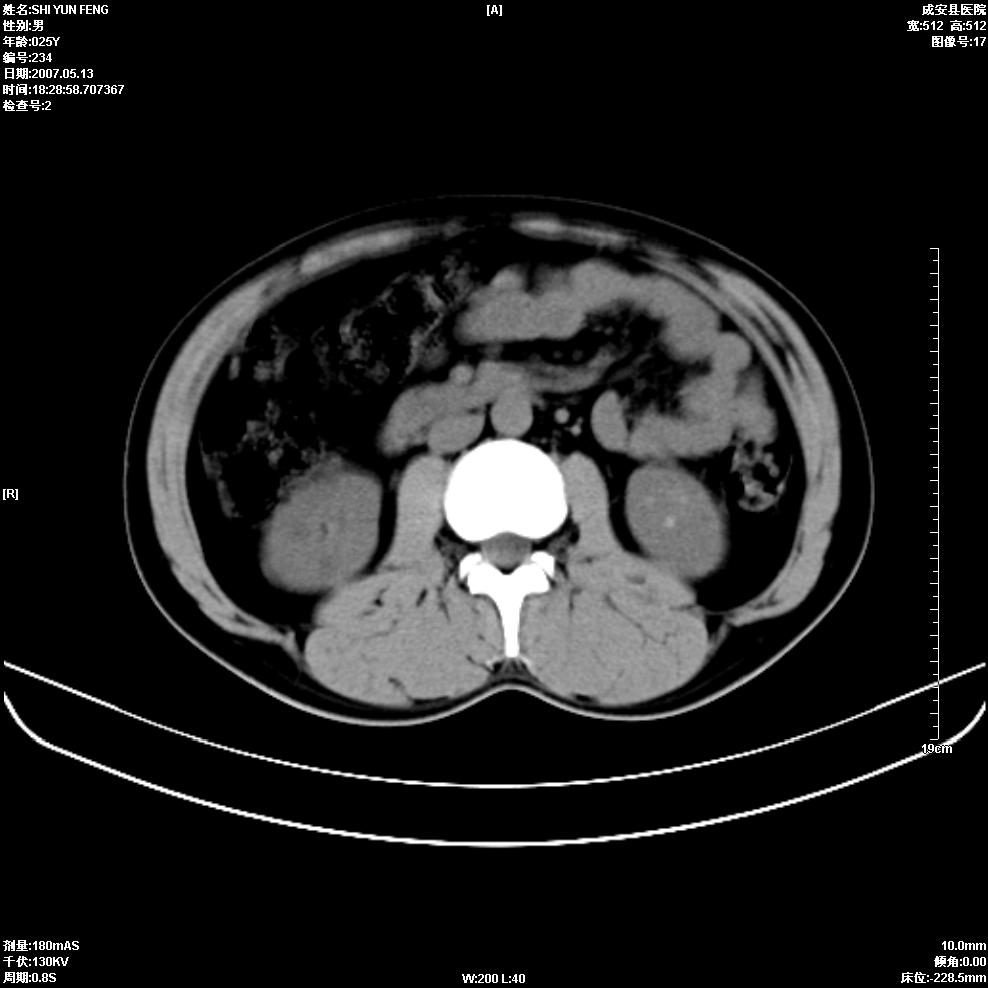

以下是引用zhangzhongshou在2007-5-16 7:36:00的发言:[br]多发性肾囊肿,左肾多发结石。不是多囊肾,楼主箭头所指多考虑左肾囊肿内结石或钙乳,髓质海绵肾不完全除外。[br][br][本贴已被 zhangzhongshou 于 2007-5-16 7:37:18 修改过][br][br][本贴已被 zhangzhongshou 于 2007-5-16 18:15:09 修改过]